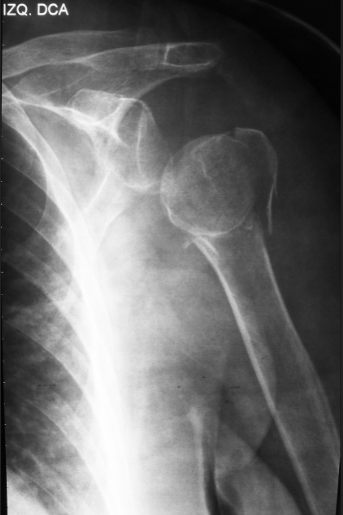

A seguir, um exemplo característico de luxação de ombro:

Luxação:

Lesão em que uma articulação é deslocada da posição normal. As articulações podem ser deslocadas devido a lesões. Geralmente, acontecem por causa de uma queda, de um acidente de carro ou durante a prática de esportes. Uma luxação é dolorosa e imobiliza a articulação. Ombros, cotovelos, dedos, tornozelos, joelhos, quadris e mandíbula são exemplos de áreas afetadas. É necessário atendimento médico imediato para colocar a articulação de volta no lugar, seguido por várias semanas de repouso.

Embora seja possível qualquer articulação se tornar luxada, os locais mais comuns em que isso ocorre no corpo humano são:

• Ombros,

• Dedos,

• Joelhos,

• Punhos (mais provavelmente acompanhado por uma fratura.)

• Cotovelos (também acompanhada por uma fratura)

• Articulação Temporomandibular (ATM).

Tratamento:

Uma articulação luxada só pode ser 'reduzida' com sucesso por um médico treinado. Tentar reduzir uma articulação sem treinamento pode causar agravamento ainda maior da lesão. Assim que o diagnóstico for confirmado, a articulação geralmente é manipulada de volta para sua posição original. Isto pode ser um processo muito doloroso, consequentemente ele é tipicamente feito sob sedação ou em uma sala de cirurgia sob anestesia geral.

É importante que a articulação seja reduzida o mais rápido possível, já que, quando deslocada, o suprimento sanguíneo para a articulação (ou para a anatomia distal) pode estar comprometido. Isso é especialmente verdade no caso de um tornozelo deslocado, devido à anatomia do suprimento sanguíneo do pé.Lesões de ombro também podem ser cirurgicamente estabilizadas, dependendo da gravidade, usando-se cirurgia artroscópica.

Para diminuir a dor do paciente, medicamentos antiinflamatórios normalmente são indicados. Algumas escolhas comuns são os antiinflamatórios não esteroidais, como diclofenaco, ibuprofeno, naproxeno, paracetamol, etc. Analgésicos também são úteis mesmo após a recolocação das articulações nos devidos locais.

Algumas articulações ficam sob maior risco de se desenvolver uma luxação novamente após uma lesão inicial. Isso ocorre devido ao enfraquecimento dos músculos e ligamentos que mantêm a articulação no local. O ombro é um exemplo clássico disso. Qualquer luxação de ombro deve ser acompanhada por ortopedista.